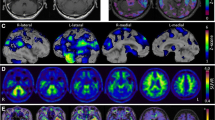

Most FDG-PET studies showed alterations in regional metabolism among PPA patients, with distinctive imaging patterns among the three PPA subtypes. A visual example can be seen in Fig. 3. The reviewed studies collectively highlight the utility of FDG-PET in identifying distinct metabolic patterns associated with different PPA subtypes, though they also reveal some discrepancies. Josephs et al. (2010) emphasized early brain changes detectable by FDG-PET, focusing on patterns of hypometabolism without using control subjects, which limited their comparative insights. Rabinovici et al. (2008) provided a more detailed account, showing distinct hypometabolism patterns specific to PPA subtypes, such as reduced metabolism in the left temporoparietal region for LPA, left frontal area for PNFA, and left anterior temporal region for SD, with significant left-sided hypometabolism (p < 0.005). Tetzloff et al. (2018) noted greater rates of metabolic change in agPPA compared to PPAOS, particularly in frontal and parietal lobes, although these results lacked statistical significance after correction for multiple comparisons. Matias-Guiu et al. (2021) demonstrated high discrimination rates between PPA patients and controls (91.67%) and among PPA variants (77.78%), yet faced challenges due to smaller svPPA patient numbers. Madhavan et al. (2013) observed specific patterns of atrophy and hypometabolism in the logopenic group, emphasizing more pronounced effects in the left hemisphere compared to Alzheimer's type dementia. Matias-Guiu et al. (2014, 2015) further corroborated these findings, noting significant inter-rater agreement and high diagnostic sensitivity and specificity, although fewer cases with PPA-S patients were a limitation.

Reproduced with permission from Matías-Guiu et al. [19]

Delineation of hypometabolic regions at [18F] fluorodeoxyglucose positron emission tomography (FDG-PET) which can aid in differentiation subtypes of primary progressive aphasia. The blue areas indicate the nonfluent/agrammatic subtype, green indicates the semantic subtype, and yellow represents the logopenic subtype.

Overall, the SD subtype exhibited hypometabolism in the left thalamus, left inferior temporal gyrus, and the fusiform gyrus. PNFA demonstrated bilateral hypometabolism in the caudate nuclei, left hemisphere, thalamus, middle and superior temporal gyri, insula/inferior frontal gyrus, pars opercularis, lateral orbital gyrus, and middle frontal gyrus. Although the LPA variant had some similar regions of hypometabolism with AD, it has also showcased hypometabolism in the lateral temporoparietal and medial parietal lobes and left frontal lobe, differing from classical AD due to unique atrophy patterns. Concurrent observations of severe hypometabolism in the left temporal areas, with a more prominent decrease in left parietal activity compared to the left temporal lobe, were evident across all PPA variants. Patients showing glucose hypometabolism in the left angular, supramarginal, and posterosuperior temporal gyri areas underscores these regions' critical role in the development of aphasia. These studies consistently support the capability of FDG-PET to differentiate PPA subtypes, though variations in sample size, patient subgroup representation, and analytical methods underscore the need for more standardized approaches and larger cohorts to refine diagnostic precision.

Another important challenge in diagnosis lies in differentiating the PPA subtypes from AD. PPA is often an early indicator of potential dementia development, with SD correlating to FTD and LPA considered an atypical AD presentation [18]. Autopsy findings revealed that around one-third of PPA patients, specifically those with LPA, demonstrated Alzheimer’s pathology [22]. The overlap of hypometabolism was evident in the medial parietal area, a hallmark of AD [18]. An example of the FDG metabolism can be seen in Fig. 4. However, in a study by Rabinovici et al., PPA patients showed greater asymmetric FDG uptake in language areas compared to AD patients [22]. In another study, the lateral temporoparietal and medial parietal lobes, and the left frontal lobe in PPA patients exhibited more pronounced atrophy and hypometabolism compared to patients with AD [22]. The similar hypometabolism patterns between LPA and AD underscores the importance of distinguishing between LPA and other PPA subtype [22, 24].

Reproduced with permission from Taswell et al. [20]

18F-FDG PET scan patterns for focal-onset dementias using Neurostat 3D-SSP where Lat lateral, LBD Lewy body dementia, Lt left, Med medial, Rt right.